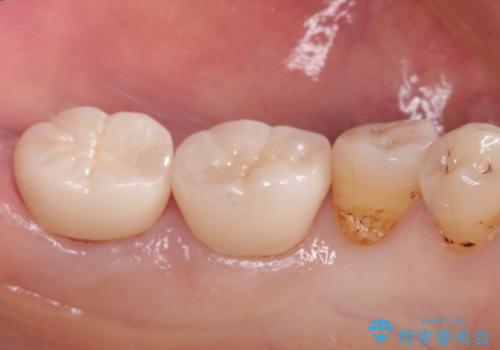

- 以前治療したところがしみて、アイスが食べられないから被せものの治療をしてほしいと来院された患者様です。

咬合が強く、歯牙にマイクロクラックが入っている状態でした。歯髄は保存可能と診断され、フルジルコニアクラウンによる治療を行いました。

咬合面に広範囲の修復物がある状態で中心に強い力が加わると歯牙は外方性の歪みが生じ、マイクロクラックができます。これを防ぐには、咬頭被覆するアンレー、もしくはクラウンによる治療が必要です。